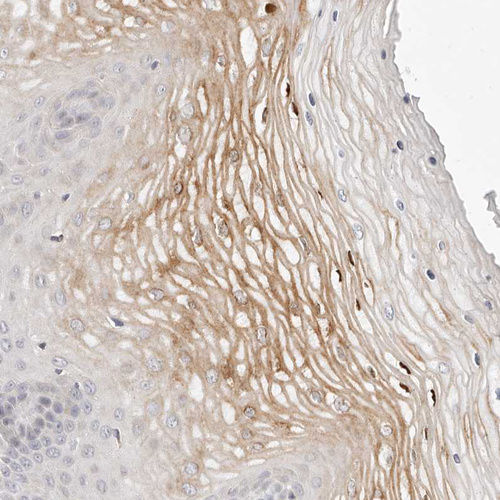

Immunohistochemical staining of human cervix, uterine shows moderate membranous positivity in squamous epithelial cells.